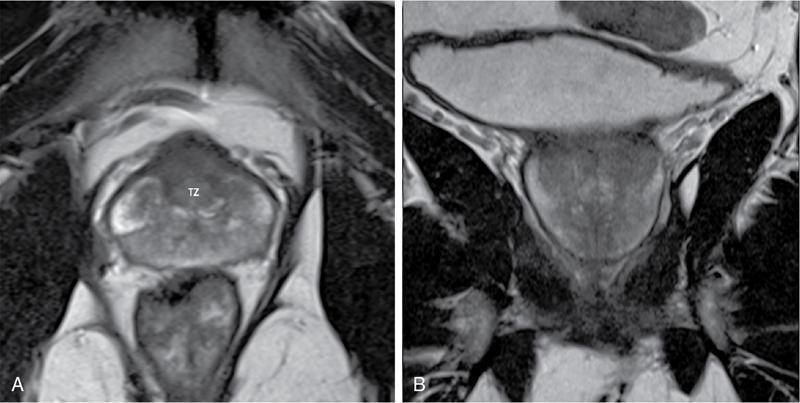

Karthik Ganesan, Disha Lokhandwala, Ujjwal Bhure, Jay Mehta Morphogenesis of the male genitourinary system is governed by the coherent interaction of three units, namely the Wolffian duct, urogenital sinus and foetal gonads. The Wolffian ducts are the embryonic precursors of the male internal genitalia, arising in the anterior intermediate mesoderm at 4 weeks of gestation. They elongate as a cord of cells that caudally extend to the urogenital sinus. Between 5 and 8 weeks of gestation, the urorectal septum divides the cloaca into a ventral compartment, which forms the urogenital sinus, and a dorsal compartment, which forms the rectum. The gonads form as epithelial thickenings on the ventromedial surface of the mesonephros and produce testosterone at 8 weeks of gestation, reaching a peak at 10–15 weeks. Under the effect of testosterone produced by the foetal testis, the prostate anlage forms at the tenth week of gestation. Precursor of the anlage begins with proliferation of solid epithelial buds from the epithelium of the urogenital septum into the adjoining mesenchyme in response to interaction of 5α-dihydrotestosterone with mesenchymal androgen receptors. As growth progresses, solid cords of epithelial cells are formed, growing into the mesenchyme in a specific three-dimensional arrangement (establishes the lobar divisions of the prostate gland). These solid cords develop a central lumen at birth and are lined by a layer of flat basal epithelium and a luminal layer of tall columnar secretory epithelium. Mesenchymal component forms the stroma, which has a large proportion of smooth muscle. Postnatally, the epithelial cords continue to arborize till puberty without any change in volume or glandular architecture. Although the foetal prostate has been described to have a histologically distinct peripheral zone (PZ) as early as 12 weeks of gestation, the mature zonal anatomy develops in concordance with the androgen surge at puberty. The most commonly utilized ultrasonographic technique for the evaluation of the prostate is via a suprapubic approach. The abdominal transducers used in this approach are relatively low frequency and while it offers the advantage of greater depth of penetration without intracavitary probe insertion; however, it does not depict the zonal anatomy and its chief application lies in volume estimation. Hence, transrectal ultrasonography (TRUS) completely outweighs the transabdominal approach in terms of depicting zonal anatomy, visualizing and localizing small lesions, demonstrating vascularity and performing biopsies. TRUS is performed using high frequency transducers (5–7.5 MHz) to optimize soft tissue resolution. An enema is administered 1 h prior to the examination to clear the field of insonation. Patient is positioned in left lateral decubitus, with knees bent toward the chest and ideally a digital rectal examination (DRE) is conducted prior to probe insertion. The transducer is first draped with a sterile barrier and lubricated, After insertion, the barrier is filled with 40–50 cc of water, making sure that no air enters. On completion, water is aspirated and the probe is withdrawn. The gland is initially scanned in the axial plane from the base to the apex, beginning at the level of the seminal vesicles, and the probe is gradually withdrawn to view the entire glandular parenchyma in axial sections up to its caudal aspect. This approach allows a cursory evaluation of glandular symmetry as both halves of the prostate can be evaluated simultaneously. Subsequently, sagittal views are acquired by rotating the probe across the transverse span of the gland, demonstrating the seminal vesicles, midline gland (visualizing both the apex and the base), with sequential scanning up to the contralateral margin of the gland. Sonographically, the prostatic capsule is seen as a smooth well-delineated, hyperechoic structure. With the newer ultrasound systems, the zonal anatomy can be delineated by TRUS; PZ appears echogenic relative to the central zone (CZ) and the transition zone (TZ), which are hypoechoic in juxtaposition (Fig. 11.12.1). Anterolaterally, the preprostatic venous plexuses are seen as anechoic tubular structures with intervening echogenic preprostatic fatty tissue. Glandular volume is estimated using an ellipsoid formula by obtaining the maximum anteroposterior, superoinferior and transverse dimensions and multiplying their product by π/6. Colour Doppler imaging is utilized to illustrate vascularity, as majority of the normal prostatic tissue (excluding the neurovascular bundles [NVBs] and pericapsular and periurethral regions) has symmetrical but sparse flow and an increased microvessel density raises the suspicion of prostatic carcinoma. However, the appearances of prostatic carcinoma can be variable on colour Doppler imaging, ranging from focal increase in vascularity around a nodule to an asymmetric increase in size and number of vessels on the affected side and conventional Doppler has found to elevate specificity by about 5%–10%. Additionally, Doppler imaging has also demonstrated some utility in distinguishing fibrotic tissue from local recurrence. However, vessels supplying cancerous tissue are of the order of 10–50 μm, which is well below the 1-mm resolution limit of conventional Doppler techniques. Contrast-enhanced colour Doppler imaging overcomes this limitation and facilitates imaging of microvessels, using intravenously administered microbubbles (less than 10 μm diameter) of an inert gas (sulphur hexafluoride) with a lipid or galactose shell, allowing quantification of blood flow in the cancerous microvessels. Additionally, these microbubbles act as vascular tracers and by monitoring the passage of a bolus injection through the tissue of interest, time–intensity curves are created. This permits the formulation of functional indices, including bolus arrival time, time to peak intensity, area under the curve and wash-in/wash-out curves. These indices can further extrapolate functional images, on a pixel-by-pixel basis, overlaid on grey-scale images. Quantitative methods to demonstrate perfusion are based on the destruction of microbubbles by high-power ultrasound pulses, and then observing the rate of microbubble replenishment in the field of interest to calculate flow rate. Halpern et al. utilized contrast-enhanced ultrasound and intermittent harmonic imaging with power Doppler, and exhibited an increment in sensitivity from 38% to 65% with a specificity of 80% in prostate cancer detection. Cadence contrast pulse sequencing (CPS) is a low-power multipulse imaging technique utilizing pulses with variable amplitudes and phases followed by a summation of the resulting echoes, permitting tissue suppression, allowing detection of even a small amount of contrast agents retained in the tissues. Real time elastosonography evaluates and quantifies tissue stiffness (Young’s modulus) by measuring strain under an applied stress (transducer compression) and maps areas of variable stiffness in colour-coded and grey-scale images simultaneously and shows potential in improving prostatic carcinoma detection. In a study comparing elastography and T2-weighted (T2-w) endorectal magnetic resonance imaging (MRI), similar sensitivity rates and negative predictive values (NPVs) were attained in the detection of prostatic carcinoma. Prostate gland is an inverted cone-shaped subperitoneal retropubic gland, with its base located rostrally and apex located caudally. The base is attached to the bladder neck and the apex sits on the urogenital diaphragm and abuts the medial surface of the levator ani muscles, namely the pubourethralis portion, which is separated from the inferolateral surfaces of the gland on either side by the prostatic venous plexus. Normal prostate gland measures approximately 4 × 3 × 3 cm, 15–20 g in weight, with a median volume of 11.5 mL (range, 1.6–20.6) in patients between 21 and 25 years and a median volume of 39.6 mL (range, 13–169.8) in patients between 38 and 83 years. The first comprehensive publication describing the anatomical subdivision of the prostate gland was in 1912 by Lowsley, based entirely on the embryonic glandular morphology at a series of gestational age groups. The budding prostatic ducts were seen to proliferate in five distinct clusters from the primitive urogenital sinus, which formed the basis of its lobar subdivision. It was divided into a ventral lobe (anterior to the urethra), two lateral lobes (lateral to the ejaculatory ducts), a posterior lobe (between the ejaculatory ducts) and a middle lobe (above the ejaculatory ducts). This classification had several shortcomings, the foremost being inclusion of only the embryonic prostate during its conception. Frank highlighted these aspects in 1953 and stated that no definite lobar boundaries exist in the adult prostate and further criticized the exclusion of periurethral glands (inner gland), identifying them as the sole site of origin of benign prostatic hyperplasia (BPH). The chief drawback of all research prior to 1968 was the lack of a concrete histological basis to support the seemingly arbitrary subdivision. McNeal was the first to ascertain histological heterogeneity within the glandular tissue and used it as the basis of his well-acclaimed prostatic zonal classification. The zonal anatomy of the prostate gland conceived by McNeal divided the gland into four distinct zones, namely the TZ, PZ, anterior fibromuscular zone (AFMZ) and the CZ (Fig. 11.12.2). McNeal used the plane of the distal urethra to describe the zonal relationships and divide the gland broadly into three parts, namely the base, midgland and the apex (Fig. 11.12.3). The improved understanding of the prostate anatomy coincided with the development of MRI in the late 1980s, which could depict the zonal anatomy, unlike ultrasonography (USG) or computed tomography (CT). Patterns of ductal growth and radiation from the prostatic urethra form the basis of the zonal anatomy of the gland. Ducts arising from the proximal urethral segment grow towards the urinary bladder. Tiny ducts which are confined by the preprostatic sphincter form the small periurethral gland, whereas ducts which develop distal to the lower border of the preprostatic sphincter extend laterally and then anteromedially to form the TZ. Ducts arising from the verumontanum in the vicinity of the ejaculatory duct orifices and are directed towards the base along the course of the ejaculatory ducts form the CZ, whereas ducts which arise from the lateral recess of the posterior urethral wall of the verumontanum and distal urethra radiate laterally to form the PZ and rostrally posterior to the CZ at the base of the gland. PZ is the dominant glandular component of the prostate gland comprising approximately 70% of the glandular tissue. On T2-w images, the normal PZ has a high T2 signal intensity (SI), owing to the abundant ductal and acinar elements with sparsely interwoven smooth muscle, and can broadly divided into three sections as per the sector map in Prostate Imaging Reporting and Data System Version 2.1 (PI-RADS v2.1), namely posterior medial, posterior lateral and anterior sections (Fig. 11.12.4). At the apex, the anterior sections have a horn-like morphology, curving anteromedially, to nearly encircle the urethra and abut the AFMZ. At the midgland level, the PZ comprises the posterior, both lateral and the anterolateral parts of the gland. At the base, the PZ is located posterior and superior to the CZ and TZ. CZ is an ovoid-shaped structure at the base of the gland, comprising approximately 25% of the glandular tissue, with its apex located at the verumontanum, surrounding the ejaculatory ducts. Beyond age 35, volume of the CZ starts to gradually diminish, as well as the CZ is compressed by the enlarged TZ. In the initial MR studies of prostate, the CZ could not be easily delineated from the TZ. Vargas et al. demonstrated in a population with a mean age of 60 years undergoing MR for prostate cancer assessment, the CZ was visible in 81%–84% of patients. Hansford et al. identified the CZ in 92%–93% of patients on T2-w images and 78%–88% of patients on apparent diffusion coefficient (ADC) maps. Histologically, substantial differences exist between the CZ and PZ, which reflect in the differential appearance on T2-w imaging. These differences are probably attributable to the differential origin, as the CZ is derived from the Wolffian duct, and the PZ and TZ are derived from the urogenital sinus. In the CZ, the acini appear larger and more irregular, with numerous epithelial covered ridges or septa project from the walls of the acini into the lumen, forming a characteristic Roman bridge architecture and intraglandular lacuna, with a prominent basal layer, crowded epithelial cells with granular eosinophilic cytoplasm, decreased luminal fluid and compact stroma. PI-RADS v2 has discouraged the use of the term central gland, as it is not reflective of zonal anatomy or reported on pathologic specimens. CZ demonstrates homogeneously low signal on the T2-w images and ADC maps and can, therefore, mimic prostate cancers. CZ is best identified on the coronal plane T2-w images paralleling the plane of the distal urethra, and appears as a symmetric paramedic paired structures surrounding the ejaculatory ducts from the base of the gland to the verumontanum (Fig. 11.12.5). TZ comprises approximately 5% of the glandular tissue of the prostate. On T2-w images, the TZ normally appears as a homogeneously hypointense structure surrounding the proximal urethra at the base and the midgland level; however, it can also demonstrate inconsistent SI, depending on the relative proportion of glandular and stromal elements (Fig. 11.12.6). Glandular hyperplasia produces higher SI (dominance of acinar elements and secretions), while stromal hyperplasia exhibits lower SI (dominance of muscular and fibrous elements). The TZ is easily demarcated from the PZ by a thick homogeneously low T2 signal surgical capsule, which becomes pronounced in BPH. With increasing age, the TZ demonstrates variegated signal on the T2-w images and ADC maps, due to differential growth of the stromal and glandular elements. AFMZ is a nonglandular muscular tissue that drapes the anterior surface of the gland, superiorly blending into the smooth muscles of the bladder neck and inferiorly extending to the prostatic urethra at the glandular apex. AFMZ is comprised of smooth muscles, which blends with the smooth muscle fibres surrounding the urethra, and rostrally merges with the bladder neck and preprostatic sphincter. High smooth muscle content of the AFMZ is responsible for the MR signature, where in it appears markedly hypointense on the T2-w images and ADC maps, and hypoenhances on the multiphase contrast series (Fig. 11.12.7). With the advancing age, temporal reduction in the size of the AFMZ is noted due to the compressive effects of the BPH. Capsule surrounds the prostate gland, anteriorly merging with the AFMZ anteriorly. Two discrete defects are identified in the prostate capsule, at the base of gland where the ejaculatory ducts enter the prostate and at the apex where in the stroma blends with the sphincter. The capsule is perforated along the anterolateral aspect by multiple vessels and nerves. The capsule appears as a thin dark rim surrounding the gland on the T2-w images and may reveal delayed enhancement on the postcontrast images (Fig. 11.12.8). Primary goal of radical prostatectomy (RP) is to achieve oncologic efficacy, both in terms of short-term and long-term clinical outcomes. However, as the majority of prostate cancers have an indolent clinical course, preservation of function in terms of continence and potency is equally important, and the key to this is a keen understanding of the fascial anatomy and neuroanatomy of the prostate gland. Fascial anatomy of the prostate gland is anatomically complex and poorly understood, and a thorough understanding of the interfacial planes is crucial to avoid mechanical or thermal injury to the NVBs. Periprostatic fascia comprises of a condensation of layers of connective tissue that encapsulate the gland and suspend it from anterior pelvic wall via puboprostatic ligaments. Laterally, the visceral and parietal endopelvic fascial layers fuse to form the fascial tendinous arch. Periprostatic fascia covers the prostate gland and capsule, comprises of two fascial layers, including an inner layer (prostatic fascia) and an outer layer (levator ani fascia), with thin interfascial planes separating these fascia from one another and the prostate capsule. Posteriorly, a continuous fascial layer known as Denonvilliers’ fascia covers the prostate and seminal vesicles. Distribution of periprostatic nerves is highly variable, with growing evidence of nerves both along the dorsolateral and ventrolateral surfaces of the prostate gland. Most of the periprostatic nerves are found posterolaterally; however, a significant portion of the nerves are located ventrally as seen by Eichelberg et al. (21.5%–28.5%) and Lee et al. (19.9%–22.8%). Although anatomic studies have confirmed the presence of ventrolateral periprostatic nerves, the exact clinical importance and functionality of these nerve fibres has not been proven. The cavernous nerves are situated posterolaterally and are the basis of nerve-sparing RP procedure proposed by Walsh and Donker. Unlike the initial theory of Walsh and Donker, few papers have proposed that the nerves are diffusely scattered along the surface of the gland in the form of a curtain or spray-like arrangement without clear bundle formation. Kourambas et al. assessed the precise relationship of the NVBs and cavernous nerves to Denonvilliers’ fascia and proposed that the nerves were not restricted posterolaterally, but were rather diffusely scattered within the fascia extending up to the midline (Lunacek et al., Takenaka et al.). On the basis of more diffuse arrangement of the periprostatic nerves, surgical techniques have been modified, resulting in a more anterior dissection called the ‘curtain dissection technique’ or alternatively a ‘superveil’ technique to preserve the NVBs within the lateral prostatic fascia. The NVB lies within areolar connective tissue surrounding the gland, which separates the capsule from the periprostatic fascia and provides a plane of dissection during nerve-sparing prostatectomy. Prostate gland is supplied and drained by periprostatic vessels, which also supply and drain the penis. Arterial supply of the gland is highly variable and is typically from branches of the internal pudendal artery, which course inferior to the gland prior to supplying the penile cavernosal tissue. Off late, these vessels have gained prominence in radiation-induced erectile dysfunction (ED) (potential vasculopathy), which have led to the development of newer vessel-sparing radiotherapy techniques. Further, with the advent of prostate arterial embolization in benign prostatic hypertrophy (BPH), the vascular supply of the gland is becoming increasingly vital to understand. Gland drains into the obturator, internal iliac, external iliac, common iliac and presacral lymph nodes. Dorsal venous complex is identified immediately ventral to the gland and also drains the penis. Periprostatic nodes are uncommon, are usually discovered near the base of the gland, and are only occasionally seen on MRI. Urethra is the principal anatomic reference point in the prostate gland. Urethra can be divided into a proximal segment and a distal segment, the point of differentiation being located at the verumontanum wherein the urethra makes an approximately 35-degree angulation. The angulation is highly variable and is further affected by the growth of the TZ. On MRI, the distal segment is more conspicuous vis-à-vis the proximal segment and appears a hyperintense core surrounded by a low signal rim on T2-w images. Preprostatic sphincter encases the proximal urethra from the base of the gland to the base of the verumontanum and merges with the AFMZ anteriorly. Verumontanum appears hyperintense on the T2-w images, lies within the distal urethral segment, beyond which the distal urethral segment is partially encircled by striated muscles which blend with the external sphincter beyond the apex of the gland. External sphincter is located distal to the apex is incomplete posteriorly and is anchored into the PZ and surrounds the membranous urethra. Damage to the external sphincter during RP or transurethral resection of the prostate (TURP) may lead to urinary incontinence. Seminal vesicles are paired structures identified posterosuperior to the base of the prostate gland, which appear as convoluted fluid-filled structures. Due to the high fluid content within the normal seminal vesicles, these structures appear as paired structures with intermediate signal walls surrounding a hyperintense core on T2-w images (Fig. 11.12.9). Vas deferens are paired structures located rostral to the base of the gland and anteromedial to the seminal vesicles and appear as cord-like structures with variable signal on the T2-w images. Duct of the seminal vesicle and vas deferens unite in the posterior aspect of the base of the gland to form the ejaculatory duct, which courses caudally to the verumontanum along the plane of the distal urethra, and drain into the orifices in the midconvexity of the verumontanum. Prostate-specific antigen (PSA) is a serine protease, secreted by epithelial cells of the prostate gland and has been found in normal, benign and malignant prostatic tissues. Traces of PSA have also been isolated from endometrial tissue, breast tissue, adrenal neoplasms and renal cell carcinomas; however, for all clinical purposes, PSA is considered as an organ-specific biomarker. Papsidero first demonstrated and quantified serum PSA, which steered the epoch of prostate cancer screening and early detection of prostatic carcinoma. Subsequent studies showed that PSA screening often led to overdiagnosis of low-grade prostate cancers, with no survival difference between the PSA screened and nonscreened groups. Additionally, PSA levels were found to be elevated in a spectrum of prostatic pathologies apart from carcinoma, including prostatitis and benign hyperplasia. The likelihood of overdiagnosis coupled with the lack of specificity set grounds for the longstanding PSA controversy. Did the benefits of screening outweigh the risks of overtreatment? To elevate the specificity of serum PSA testing, a plethora of indices were devised, including free PSA and total PSA, free-to-total PSA (f/t PSA) ratio, age-specific PSA, PSA velocity (PSA-V) and PSA density (PSAD). Serum PSA exists in three forms; the major form (approximately 75%) is bound to alpha-1-antichymotrypsin, followed by free PSA (constituting 5%–50% of serum PSA). The third form (PSA bound to alpha-2-macroglobulin) is not clinically relevant and cannot be detected by any commercial test. A study by Stenman et al. established that a higher proportion of bound PSA and hence a lower ratio of f/t PSA is associated with prostate cancer. Conversely, free PSA can be utilized during follow-up for men with an initial negative biopsy result, wherein declining free PSA with a persistently elevated total PSA would raise suspicion of a neoplastic aetiology. As per the ACS guidelines (Table 11.12.1) for early detection of prostate cancer, men with a 10-year life expectancy or higher should have the opportunity to make an informed (regarding benefits, risks and uncertainties associated with PSA screening) decision for serum PSA testing, with or without DRE. For those who choose to undergo PSA screening, subsequent screening interval is determined on the basis of baseline PSA value. For values below 2.5 ng/mL, screening interval can be extended to 2 years and for PSA between 2.5 ng/mL and 4 ng/mL, an individualized approach is adopted following risk assessment to recommend either further referral or screening on a yearly basis. A PSA level of 4 ng/mL or higher warrants referral for further evaluation or biopsy, for men at average risk for prostate cancer. Although age-specific PSA (Table 11.12.2) is not a component of the ACS guidelines, it is considered as a beneficial parameter in determining the need for biopsy. As there is an expected rise in PSA values with age, setting a lower cut-off value for younger men would increase the sensitivity of detecting organ confined cancers and a higher value in older men would increase specificity. aThere is no proven rationale for using a single PSA-V threshold value. PSA screening guidelines for treated localized prostate cancers are variable and the definition of biochemical (PSA) recurrence remains debatable. Due to this inconsistency, the Prostate Cancer Guidelines Update Panel recommended a standard definition for biochemical recurrence (BCR) after RP and set a cut-off serum PSA (acquired between 6 weeks and 3 months of surgery) of 0.2 ng/mL or greater, along with a second confirmatory PSA. While there is a significant fall in PSA values after RP and a single raised PSA is sufficient to raise suspicion of recurrence, postradiotherapy recurrence requires a rising trend rather than a single cut-off value. The ASTRO Consensus Panel defined postradiotherapy prostate cancer recurrence as three consecutive raises in PSA values after a baseline has been reached. A hiatus in this definition was that no specific time interval between consecutive increases in PSA was determined. In addition to its utility as a screening tool, PSA is also a good prognosticator when used in conjunction with biopsy Gleason score and clinical T-stage, and several pretreatment prostate cancer risk stratification systems are based on these indices. D’Amico et al. proposed a three-group risk stratification system in 1998, which categorized nonmetastatic (M0) carcinomas as low risk, intermediate risk and high risk. Low-risk prostate cancer was defined as 1992 AJCC T1/T2a, PSA ≤10 ng/mL and Gleason score ≤6. Intermediate-risk prostate cancer was defined as 1992 AJCC T2b, and/or PSA 10–20 ng/mL and/or Gleason 7 disease. High-risk disease included any one of the following: 1992 AJCC ≥T2c, PSA >20 ng/mL or Gleason 8–10 disease. In 2001, the GUROC published the results of a consensus meeting which categorized the groups as follows: low risk – 1997 AJCC T1–T2a, PSA ≤10 ng/mL and Gleason ≤6; intermediate risk – 1997 AJCC T1–T2, PSA ≤20 ng/mL and Gleason ≤7 not otherwise low risk and high risk – 1997 AJCC T3–T4 or PSA >20 ng/mL or Gleason 8–10. In due course, newer classification systems have been developed (Table 11.12.3), including the National Comprehensive Cancer Network (NCCN, USA), National Institute for Health and Clinical Excellence (NICE, UK), European Society of Medical Oncology (ESMO), American Urological Association (AUA) and the European Association of Urology (EAU). The NCCN guidelines also incorporate very low-risk (T1c, and Gleason score ≤6, PSA ≤10 ng/mL, <3 positive biopsy cores each ≤50% involved and PSAD of <0.15 ng/mL/g) and very high-risk (T3b–T4) categories. AUA, American Urological Association; EAU, European Association of Urology; GUROC, Genitourinary Radiation Oncologists of Canada; NICE, National Institute for Health and Clinical Excellence; CAPSURE, Cancer of the Prostate Strategic Urologic Research Endeavour; NCCN, National Comprehensive Cancer Network; ESMO, European Association of Urology; T, T-stage; GS, Gleason score; PSA, prostate-specific antigen. Note: Use of the 1997 TNM staging system (T2a one lobe involvement, T2b two lobes involvement, no T2c category). PSA, DRE and TRUS form the diagnostic triad for prostatic carcinoma. It has been well established that manipulations of the prostate gland, including prostatic massage, cystoscopy and perineal biopsy cause a potential increase in serum PSA levels. This raised the question of TRUS affecting PSA levels and it was found to cause a very small rise in PSA only in patients with prostatitis. The effect of DRE on serum PSA levels is also controversial, while some studies found a transient increase in PSA, others found no significant rise in PSA levels after DRE. Therefore, it is advisable to obtain blood samples for PSA testing either prior to DRE and TRUS or after at least 7 days. PSA-V refers to the change in PSA over time using serial measurements. Ideally, at least three consecutive measurements over at least 18–24 months should be used. Carter et al. first defined PSA-V and found that a value of 0.75 ng/mL per year or greater was indicative of carcinoma with a high sensitivity and specificity. Consequently, several studies disproved a definite relationship between PSA-V and prostate cancer, stating that there was no rationale behind a single threshold value for PSA-V. Further, it was found that calculating PSA-V was arduous and while elevated PSA values on serial examinations should raise alarm, there was no added benefit of formally calculating PSA-V. As per NCCN guidelines, the PSA-V cut-off should be based on the initial PSA value with a PSA-V of 0.35 ng/mL/y, when the PSA is ≤2.5 ng/mL and 0.75 ng/mL/y, when the PSA is 4–10 ng/mL PSAD was developed in order to correlate prostate volume and PSA values. The basis of PSAD was that cancer cells produce more PSA per unit volume than normal cells. It is calculated as PSA value divided by the prostate volume as determined by TRUS. This reliance on TRUS leads to interobserver variability and hence PSAD values would differ with the performing sonologist. The chief utility of PSAD is in the diagnostic grey zone of PSA values between 4 and 10 ng/mL and the most commonly used cut-off value is 0.15 ng/mL/cc. However, more recent studies have shown that a value of 0.08 ng/mL/cc has an NPV of 95% in predicting prostate cancer. Additionally, PSAD in conjunction with MRI (PI-RADS score) has proved to be a reliable prognosticator for Gleason score upgrading. The most significant application being avoiding unnecessary biopsies as PI-RADS scores of 1–3 along with PSAD values <0.15 ng/mL/cc showed no Gleason score upgrading on repeat biopsies. In summary, most guidelines recommend shared decision-making for screening of prostate cancer. Limited testing should be conducted in men with low PSA values and a lower life expectancy. The aim should be to overcome challenges posed by the inherent nonspecific nature of serum PSA and reduce superfluous testing, unwarranted biopsies and overdiagnosis. Reliance on parameters like PSA-V that do not have a proven scientific basis is avoidable. Whereas applications of PSA like PSAD along with MRI can greatly reduce patient burden by avoiding follow-up biopsies. Lastly, PSA has no role in assignment of a PI-RADS category, which is based on multiparametric MRI (mpMRI) findings alone. Several ‘novel biomarkers’ are now being developed which are more specific in detecting high-grade prostatic carcinomas. Other human kallikrein proteins have been identified, as prostate cancer biomarkers, of which, human kallikrein 2 (hK2) has shown a high specificity. While hK2 and PSA have an overlapping primary structure, malignant cells express hK2 to a higher degree than benign epithelial cells, particularly in aggressive cancers. Engrailed-2 (EN2) is an HOX gene family transcription factor seen exclusively in malignant prostate tissue, with a reported sensitivity and specificity of 66% and 88%, respectively. Annexin A3 is a calcium-binding protein measured in urine samples following prostatic massage, potentially reducing unnecessary biopsy in men with a PSA of 2–10 ng/mL. However, extensive prospective evaluation of these biomarkers is necessary to replace PSA testing in clinical practice. Positron emission tomography (PET)/CT has evolved over the last two decades to make a paradigm shift in the field of imaging, moving from morphological imaging to molecular level and completely changing the approach to how we view the disease. Though the main workhorse tracer in the field of PET/CT is 18-fluorine-fluorodeoxyglucose (18F-FDG), it has limitations with regard to prostate cancer, especially in indolent or well-differentiated ones. However, that void has been filled up by the new kid on the block and that is prostate-specific membrane antigen (PSMA)-based radiotracer. PSMA is a type II transmembrane protein with intracellular (19 amino acids), transmembrane (24 amino acids) and extracellular (707 amino acids) domains, which functions biochemically as a glutamate carboxypeptidase. After a ligand binds to PSMA, internalization occurs and it is either retained in lysosomal compartments or released into the cytoplasm. PSMA expression and localization in the normal human prostate is associated with cytoplasm and apical side of the epithelium surrounding prostatic ducts but not basal epithelium and neuroendocrine or stromal cells. Neoplastic transformation of prostate tissue results in the transfer of PSMA from the apical membrane to the luminal surface of the ducts. PSMA is an ideal target for molecular imaging of prostate cancer as its expression is significantly upregulated in prostatic carcinoma cells compared to benign prostatic tissue, in density (100 to 1000 times) as well as activity (8 to 10 times). PSMA expression increases with increase in Gleason score, stage and grade of tumour, with further increased expression with transition to androgen-independent/castration-resistant prostate cancer. PSMA-binding analogues, because of their high sensitivity and specificity, possess precise imaging characteristics required for critical decisions in the management of prostate cancer (PCa). The most commonly used PSMA radiotracer is 68Gallium-PSMA-11, followed by 18F-PSMA. The availability of 18F-labelled PSMA radiopharmaceutical has helped to advance the reach of PSMA PET imaging to wider locations owing to higher available amount of the radiotracer due to its production from a cyclotron, compared to 68Ga-PSMA which is eluted from individual in-house generator. Additional benefit is accrued with excellent image quality owing to optimized radiotracer doses, higher imaging statistics and favourable decay properties of 18F radioisotope. The normal physiological biodistribution of PSMA-based radiotracers is seen in lacrimal and salivary glands, liver, spleen, kidneys and intestine. Physiological activity is also seen in celiac and cervicothoracic ganglia. Unbound PSMA radiotracer is excreted by the kidneys into the urinary bladder. PSMA PET/CT has established roles of varying degrees in the imaging of different aspects of prostate cancer including primary diagnosis, staging, BCR after primary prostate cancer treatment (prostatectomy), identification and significance of oligometastasis, restaging and treatment response assessment and monitoring. PSMA PET/CT is useful at the stage of diagnosis in that subset of patients with tumour-negative biopsy samples, by contributing the useful molecular information to mpMRI, helping to precisely delineate suspicious lesions for targeted biopsies. In intermediate-risk to high-risk primary prostate cancer patients, PSMA-based imaging has shown improvement in detection of metastatic disease compared to the CT and mpMRI, which has led to reduced demand and dependence on additional cross-sectional imaging or bone scintigraphy. Furthermore, PSMA PET/CT has also established its clear advantage over conventional imaging in patients with biochemically recurrent prostate cancer with improved and increased detection of metastatic sites even at low serum PSA values. As it happens in cancer, biopsy is the standard of diagnosis and likewise in PCa, it is the multicore biopsy, which is the gold standard. However, because of its size, location, approach and sensitive and delicate nature, yield and accuracy can often be restricted, especially in inexperienced hands. The diagnostic yield of biopsy can go down as low as 40% and false negative (FN) rate can climb as high as 25%–30%. PSMA overexpression follows high-grade PCa cells and increases with Gleason score. In normal prostate tissue, PSMA to PSA ratio is about 1, which decreases in BPH, increases in primary PCa cells, further increases with intratumoural angiogenesis, higher in metastatic lesions than in primary PCa cells and further upregulated in castration-resistant situation. In a study by Litwin and Tan in 2017, the FN rate of multicore biopsy was around 21%–28% and about 15% of the cases were undergraded vis-à-vis final prostatectomy results. While the diagnostic accuracy of random multicore biopsy was around 76.3%, that of 68Ga-PSMA PET/CT was upward in the range of 85.5%. The role of PSMA PET/CT in the primary/initial diagnosis of prostate cancer is generally limited to clinically intermediate-risk to high-risk patients with negative biopsy or reluctance to biopsy or noncooperation or nonfeasibility and for confirmation and staging in clinically high-risk patients. In low-risk patients, metastatic spread is very unlikely and hence it is a relative indication at the time of initial diagnosis in low-risk patients. And, its role in screening is variable and debatable (Fig. 11.12.10). Staging is crucial as it has considerable influence on deciding further line of management and treatment choices, which includes RP, radiotherapy or palliative systemic treatment, deciding on the extent of the pelvic nodal dissection during surgery, planning the radiotherapy field and consideration of multimodal therapy. Accurate staging helps to make the most appropriate choice of treatment modality (Fig. 11.12.11). In a meta-analysis of five studies with histopathology as gold standard, which included 216 patients, the per-lesion sensitivity of 68Ga-PSMA PET/CT ranged from 33% to 92% (33% value being an outlier due to the retrospective analysis based only on the reports, in absence of the images) with higher specificity of 82%–100%. For T-staging, PSMA PET/CT showed a significantly higher tumour detection rate of 92% vis-à-vis 66% with MR alone. In regard with N-staging, the majority of metastatic nodes from prostate cancer are small subcentimetre-sized, less than 8 mm, which are overlooked, missed or inconclusive on morphological imaging (CT and MRI) (falling below size criteria for morphological imaging). Accurate N-staging is important because lymph node involvement is a critical prognostic factor in cancer management, and precise pelvic nodal clearance could be curative and could make a difference in treatment success and long-term outcome in prostate cancer (Fig. 11.12.12). Also, accurate prediction of pelvic nodal metastases may spare nodal dissection, shorten surgical time and in turn help to reduce undesirable complications. In one study from 2016 involving 130 patients with intermediate-risk to high-risk prostate cancer, the metastatic nodal detection rate by 68Ga-PSMA PET was around 66% compared to 44% with MRI. PSMA PET has shown superior predictive value for surgical response over Gleason score, pT stage and PSA (at the time of imaging). In a literature overview by Luiting et al. in 2019 involving 9 retrospective and 2 prospective studies, the specificity of PSMA PET/CT in detection of pelvic nodal metastases before initial treatment reached as high as 80%–100%. PSMA PET/CT increases the confidence level in the evaluation of nodal metastases and an NPV reaching up to 86%. With imaging becoming more precise and adding different modalities together, the question arises about the tiny nodes less than 5 mm size. In a study by van Leeuwen et al. in 2017, the mean size of missed lymph node metastases was 2.7 mm. In a recent study by Ferraro et al. in 2020, about the impact of PSMA PET staging on clinical decision-making in intermediate-risk to high-risk prostate cancer patients, PSMA PET provided new information in 36% of patients and this helped to change treatment decision in nearly 27% of patients, which means in every fourth patient they studied. PSMA PET in combination with CT or MRI can achieve complete and precise Tumor, Nodes and Metastases (TNM) staging including staging of local tumour, nodal assessment and bone and organ/visceral metastases, in one single imaging session, with improved accuracy and better outcome, and in turn leading to precise treatment planning, eventually superseding conventional imaging. Accurate localization of prostate cancer lesions in patients with BCR is a major challenge. Especially at low serum PSA values (as low as less than 0.5 ng/mL), the precise determination of localized disease and metastatic spread is of great importance for further disease management. Conventional imaging modalities including CT scan or bone scintigraphy have limited detection rate for metastatic disease at low serum PSA values in this setting of BCR. PSMA PET/CT imaging plays a very valuable role in the evaluation of BCR (Fig. 11.12.13), which is indeed very critical and important aspect in prostate cancer management. The international consensus on BCR includes PSA >0.2 ng/mL for two times after prostatectomy, or PSA nadir + 2 ng/mL after radiotherapy or brachytherapy. With the incorporation of PSMA PET/CT in the imaging armamentarium, the overall detection rate for local recurrence as well as metastases with BCR after prostatectomy reached up to 90%. The detection rate increases with rising PSA level, jumping over 90% with PSA level going above 1 ng/mL. In a homogeneous consecutive cohort of 248 patients with BCR after RP with mean serum PSA value of 1.99 ng/mL, studied by Eiber et al., 68Ga-PSMA PET/CT showed detection rates of 57.9%, 72.7%, 93.0% and 96.8% for patients with serum PSA values of 0.2–<0.5 ng/mL, 0.5–<1 ng/mL, 1–<2 ng/mL and ≥2 ng/mL, respectively. Tumour Gleason score or androgen deprivation therapy (ADT) did not significantly influence the detection rates (Fig. 11.12.14). These detection rates for 68Ga-PSMA PET are substantially higher than those reported for choline-based PET radiotracers, which fell between 19% and 36% at serum PSA levels of <1.5 ng/mL. The improved detection rates are due to the incremental value of molecular imaging as 68Ga-PSMA PET exclusively showed findings not evident on diagnostic CT in 32.7% of patients with information about additional involvement of different anatomical region in 24.6%. A high PSA-V and short PSA doubling time showed a tendency towards increased detection rates, though not statistically significant. As salvage radiotherapy is most effective at low serum PSA values, optimized radiotherapy planning with precise definition of target volume for concerned lesions for appropriate boost radiotherapy can be achieved with the help of PSMA PET/CT imaging. Lesion detection rate with PSMA PET/CT in the setting of BCR: PSMA PET/CT imaging helps to identify patients with oligometastatic disease who are suitable for salvage therapy with PSMA-radioguided surgery. PSMA radioligands, by the virtue of their high sensitivity and specificity, can be used for intraoperative tracking of even small metastatic prostate cancer lesions that can be well localized and subsequently removed using this radioguided surgery for salvage procedures. Identification and treatment of oligometastatic disease (3 to 5 positive sites) with targeted therapies such as surgery or radiotherapy may allow deferral of systemic therapies such as ADT, thereby delaying and reducing potential morbidity associated with systemic salvage therapy. The fusion of PSMA PET and MRI, instead of CT, may improve detection rates further in patients with very low serum PSA values (<0.5 ng/mL). The addition of mpMRI to PET can improve the diagnostic accuracy because of the higher soft tissue resolution and detection efficacy of mpMRI for local recurrence compared to CT. Advantages of PET/MRI include excellent anatomical and zonal resolution of the prostate gland with T2-w sequences, and additional useful information about suspicious lesions from functional MRI sequences like diffusion-weighted images (DWI) and dynamic contrast-enhanced (DCE) imaging. Early and accurate detection of tumour burden helps to plan further management strategy including salvage pelvic radiotherapy or salvage nodal dissection and eventually improve the prognosis. PSMA PET/CT also plays an important role in mapping the overall tumour burden, and separating oligometastatic disease from multiple metastases (Fig. 11.12.15). PSMA PET/CT also plays an important role in monitoring the treatment efficacy as well. 99mTc-methylene diphosphonate (99m Tc-MDP) (gamma camera-based radiotracer – single-photon emission computerized tomography (SPECT)/CT) or 18F-sodium fluoride (NaF) (PET/CT-based radiotracer) are bone-specific biomarker of osteoblastic activity. 18F-NaF has superior diagnostic performance compared to 99mTc-MDP (phosphonates) bone scintigraphy in detection of bone metastases, because of different radiotracer characteristics (different energy levels) and different scanners (PET/CT scanners vs conventional gamma scanner) leading to better resolution and clarity with 18F-NaF PET/CT scans. NCCN recommends bone scintigraphy in patients with PSA levels of more than 20 ng/mL or patients with T2 disease with PSA levels more than 10 ng/mL. However, their routine use in clinical practice is limited by relative lack of sensitivity and specificity vis-à-vis PSMA PET/CT and also not able to assess soft tissue lesions, which is possible with PSMA PET/CT (Fig. 11.12.16). Bone scans often fail to detect a lesion when PSA is less than 10 ng/mL in the setting of PSA recurrence post-RP, whereas PSMA PET/CT has been sensitive in the detection of lesions even at the PSA level of less than 0.5 ng/mL. Prostate cancer is a leading cause of cancer-related death in men; however, many patients with the prostate cancer do die of other causes. Hence, it is of paramount clinical importance to accurately risk stratify patients, to distinguish those with low risk to intermediate risk who could be managed conservatively or alternatively those with high risk for morbidity and mortality who would benefit from an aggressive line of therapy. Detection, risk stratification, staging, individual centred management, monitoring and surveillance of prostate cancer have undergone substantial evolution with time. MRI of the prostate gland was first described by Hricak et al. in 1983 and for long was used for staging patients with biopsy-proven prostate cancer and also occasionally served as a problem-solving tool. With recent advancements in MR technology, multiparametric imaging has become the cornerstone of the prostate cancer management, aiding in detection, characterization, risk stratification, biopsy guidance, surveillance and monitoring. This has been further enhanced and strengthened with the introduction of PI-RADS v2.0 in 2015 which helped standardize communication between the radiologists and urologists, and aided in the clinical decision-making process. As the role of MRI has expanded from detection to surveillance and monitoring, the entire clinical context needs to be available to the radiologist prior to performing an mpMR in order to optimize reporting. Both the imaging techniques and its interpretation may vary with the clinical context. In patients with no prior history of therapy, both T2-w images and DWI have a greater impact on reporting and interpretation, whereas in patients with prior therapy T1-w DCE imaging plays a more critical role in interpretation. In routine clinical practice, PI-RADS v2 recommends that PSA levels, detailed results of prior prostate biopsies and therapies be available to the radiologist at the time of performing and interpreting MR findings. Postbiopsy intraglandular haemorrhage occurs after image-guided prostate biopsies and is a confounder, which may obscure an underlying cancer. The greater extent of haemorrhage is attributable to the production of citrate within the prostate gland, which acts as an anticoagulant. The rate at which haemorrhage resolves is highly variable, often fully resolving in a shorter period in some patients and alternatively persisting for many months. Haemorrhage exclusion sign is a useful imaging finding, which may allow the radiologist to localize prostate cancer, as cancerous tissue has low levels of citrate and hence the propensity to haemorrhage in cancerous tissue is lower vis-à-vis benign glandular tissue. In addition, postbiopsy haemorrhage produces milder hypointensity on the T2-w and ADC maps vis-à-vis cancerous tissue. Ideally, a timeframe of 6–8 weeks has been suggested between the biopsy and the mpMRI. However, in routine clinical practice, the need to accommodate patients immediately postbiopsy or within a shorter time frame does exist, as the information provided by mpMR does overweigh the impact on haemorrhage on intraglandular tumour detection. Rectal over distension with faecal matter or gas impairs the quality of prostate mpMRI and especially seems to exacerbate artefacts on DWI. These issues seem to impact imaging with phased array coil rather than endorectal examinations. To avoid these artefacts, patients may be instructed to evacuate shortly before the examination, use a laxative or minimal enema prior to the procedure, have a preparatory enema or use antispasmodic agents to reduce potential artefacts from bowel peristalsis. Though various approaches do exist to adequately empty the rectum and minimize the artefacts, there is a lack of consensus on the optimum technique. mpMRI of the prostate gland can be performed on a 1.5 Tesla (1.5 T) or a 3 Tesla (3 T) scanner. Vastly improved signal-to-noise ratio (SNR) is the critical advantage of a 3 T scanner over a 1.5 T scanner, which in terms of prostate imaging translates into acquisition of high quality images with improved spatial and temporal resolutions, and also acquisition of higher quality functional sequences for quantitative imaging. Therefore, increasing field strength results in better detection and characterization of prostate cancer. On the contrary, higher field strength can amplify susceptibility artefacts arising from rectal air or metallic prosthesis. Other than field strength, many factors impact image quality and resolution including scanner model, gradient quality, slew rate, coil architecture and design and the sequence MR acquisition parameters. Prostate examinations are performed using a phased array coil placed over the pelvis. In certain institutions, an additional endorectal coil may also be used to achieve a higher SNR which improve the visualization of the prostate capsule and NVBs. Utilization of endorectal coils has certain drawbacks and results in patient discomfort, increased cost and scan duration and causes gland distortion. Endorectal coils improve imaging quality and local staging; however, with recent advances in coil technologies, phased array surface coils do provide similar high quality resolution images, which allows for accurate local staging. Currently, PI-RADS v2.0 does not insist on the use of endorectal coil and allows radiological practices to select hardware and optimize sequences that are most appropriate for the given clinical setting. mpMRI of the prostate gland is a combination of anatomical (morphological) and functional sequences. As per the PI-RADS v2 guidelines, the key sequences recommended include triplanar high-resolution axial T2-w images, high b-value axial DWI and ADC map and axial T1-weighted (T1-w) DCE images. High-resolution axial T2-w images and DWI are used to initially localize the ‘index lesion’ in the prostate gland. High-resolution sagittal and coronal T2-w images aid in colocalization of the ‘index lesion’ in terms of its spatial relationship with the gland. High-resolution T2-w images are the principal sequences of mpMR and are acquired with a small field-of-view (120–140 mm) in sagittal, oblique axial and oblique coronal planes. The high-resolution oblique axial and oblique coronal T2-w images are acquired orthogonal and parallel to the long axis of the prostatic urethra. These anatomical images provide exquisite demonstration of prostatic zonal anatomy, prostate capsule and periprostatic structures, which allows to accurately detect extraprostatic extension. An alternative to the acquisition of three separate T2-w sequences is the acquisition of a single volumetric 3-D T2-w imaging sequence with small near-isotropic voxels, which can then be retrospectively reconstructed in any plane. However, few concerns regarding the 3-D acquisition exist, including long acquisition time that may predispose to greater motion artefacts, reduced in-plane resolution and superimposed T2 and T1 contrast, which may diminish lesion conspicuity. PZ: Normal PZ has high SI on the T2-w images due to its high water content. Most prostate cancers exhibit low SI on T2-w images; however, mucinous adenocarcinomas may have a predominantly high SI. Low SI in the PZ may appear focal or diffuse and is not sine qua non for cancer, and may be seen in chronic prostatitis, glandular atrophy, postbiopsy haemorrhage or represent posttreatment sequelae. Rosenkrantz et al. demonstrated a diagnostic accuracy of 60% for T2-w imaging and showed that T2-w images is only moderately accurate for the detection of cancer and is not adequate for the diagnosis and localization of prostate cancer. T2-w images exquisitely demonstrate important morphological features of the lesion, which may aid in differentiation of cancerous tissue from its benign mimics, including size, shape and margin. Morphological features may overlap between benign lesions and low-risk to intermediate-risk cancers, but are very conspicuous in high-risk cancers. Benign lesions tend to appear linear-shaped or wedge-shaped and have indistinct margins, whereas prostate cancer appears as focal, crescentic or lentiform-shaped lesions. Lesion size is also a predictor for benign versus malignant, with larger lesions more likely to represent prostate cancer with a greater propensity to develop extracapsular extension. T2-w imaging is not the dominant sequence used to assess lesions in the PZ. T2-w PI-RADS v2 categories for PZ lesions are based on the SI, size, shape and margin of the lesion. PI-RADS category 1 is assigned to a homogeneously high SI normal PZ. PI-RADS category 2 lesions are linear-shaped or wedge-shaped, or present as areas of mildly low SI with indistinct borders. PI-RADS category 3 lesions have moderately low SI, but are heterogeneous or noncircumscribed are considered indeterminate. PI-RADS category 4 lesions have a high probability for clinically significant prostate cancer, are focal mass-like, circumscribed, exhibit homogeneously moderate to marked low SI and are less than 1.5 cm in size and do not exhibit extracapsular extension. PI-RADS category 5 lesions have a high probability for clinically significant prostate cancer, are focal mass-like, circumscribed, exhibit homogeneously moderate to marked low SI, are greater than or equal to 1.5 cm in size and/or exhibit extracapsular extension. Findings of extraprostatic extension (EPE) include focal capsular bulge with whiskering of the periprostatic fat, capsular irregularity, NVB asymmetry, obliteration of rectoprostatic angle and seminal vesicle invasion (SVI). TZ: Accurate detection and characterization of focal lesions in the TZ is the greatest challenge in the assessment of mpMRI. The challenge is most profound in middle age and elderly patients, the same population subset at risk for developing prostate cancer. T2-w imaging is not the dominant sequence used to assess lesions in the PZ. T2-w imaging is the dominant sequence used to assess lesions in the TZ in view of its ability to assess lesion texture and margins. BPH affects the periurethral TZ and glandular tissue and is characterized by the development of multiple variable size encapsulated nodules exhibiting variegated T2 signal due to the differential proportions of stromal hyperplasia and glandular hyperplasia, termed as organized chaos. Stroma rich BPH nodules pose a serious diagnostic challenge as this entity appears as low SI on T2-w images and hence lesion morphology plays a pivotal role in distinguishing this entity from prostate cancer. PI-RADS category 1 is assigned to a homogeneously intermediate SI normal TZ (Fig. 11.12.17). PI-RADS category 2 lesions are well-circumscribed and encapsulated nodules with low or heterogeneous T2 SI and are typically benign (Figs. 11.12.18 and 11.12.19). PI-RADS category 3 lesions are considered indeterminate, exhibit heterogeneous SI with obscured margins and are of any size (Fig. 11.12.20). PI-RADS category 4 lesions have a high probability for clinically significant prostate cancer, are lenticular or indistinct foci of homogenous moderately low SI, are less than 1.5 cm in size and do not exhibit extracapsular extension (Fig. 11.12.21). PI-RADS category 5 lesions have a high probability for clinically significant prostate cancer, are lenticular or indistinct foci of homogenous moderately low SI, are greater than or equal to 1.5 cm in size and/or exhibit extracapsular extension (Fig. 11.12.22).